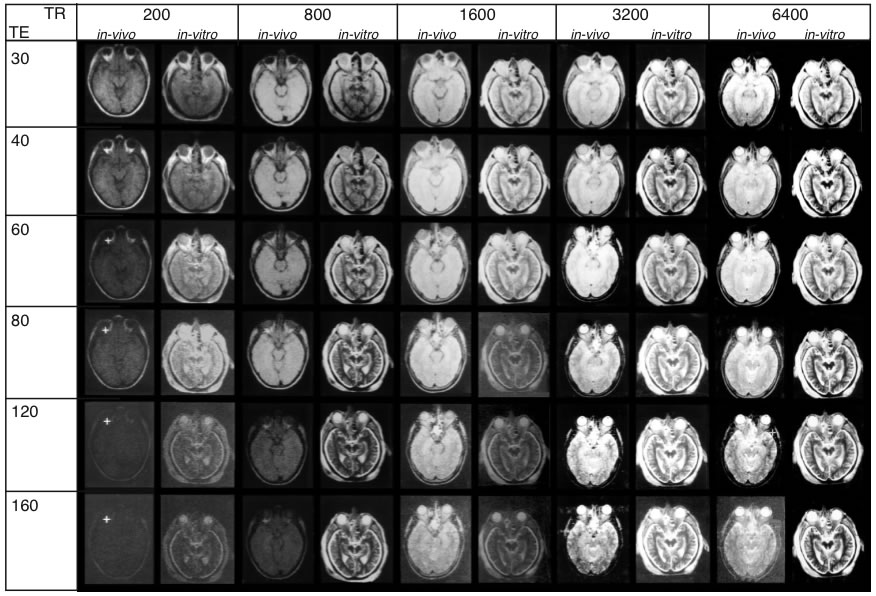

In autopsy brains, relaxation times, signal-to-noise ratio, and contrast are altered due to absence of flow effect, cessation of metabolism and fixation procedures. In order to perform comparison analysis between living and postmortem tissue, parameters that influence signal intensity were measured under both in vivo and in vitro conditions. For such a correlation, the heads of two volunteers and of two cadaver heads were scanned. The parameters of the IR and SE sequences and corresponding images of one image plane are shown in Fig. 1.

Figure 1 – B

TR and TE (spin-spin relaxation) times for SE sequences. MR images obtai

ned under in vivo and in vitroconditions exhibit striking

differences. Upper inset (A) shows the plane of sectioning. The lower inset shows every scan overlayed with

a grid (A-F) to secure precise location of the same regions of interest throughout the series. (Abbreviations:

CP: cerebral peduncle, GM: gray substance), Hi: hippocampus, Li: cerebrospinal fluid, OF: orbital fat, ON: optic

nerve, RN: red nucleus, TM: temporalis muscle, VB: vitreous body, WM: white matter.